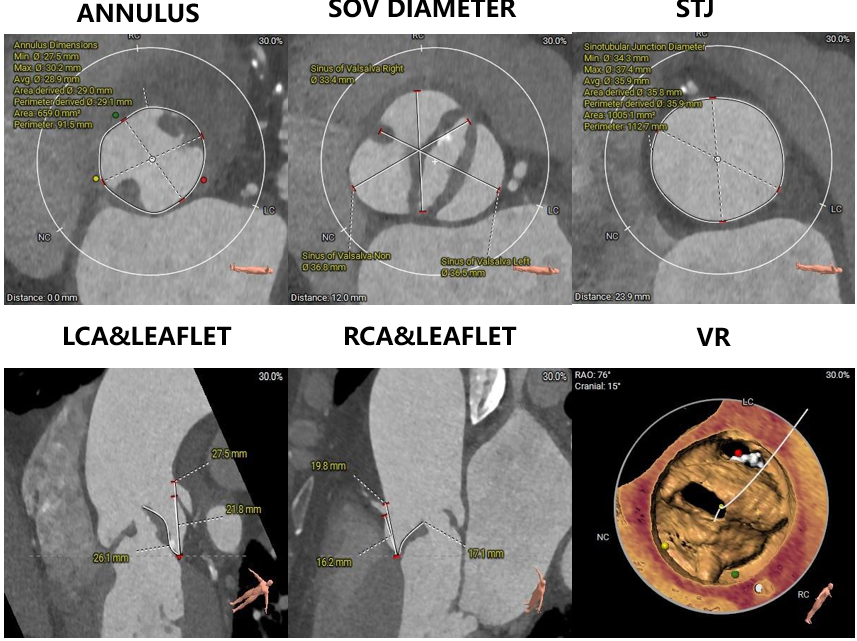

主动脉根部评估

瓣环上解剖结构评估

术前评估

1.主动脉瓣瓣环周长90.6mm,平均周长径28.8mm。

2.主动脉瓣成三叶式,瓣叶明显增厚伴重度钙化,钙化均匀分布与三窦瓣叶上。

3.左右冠脉开口高度可。

4. 左室腔内径较大,心室壁厚度可,横位心,升主动脉扩张。

5.双侧股动脉入路血管管径良好。